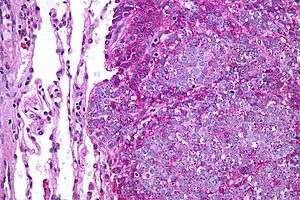

| Micrograph of metastatic Ewing sarcoma (right of image) in normal lung (left of image). PAS stain. | |

The definitive diagnosis is based on histomorphologic findings, immunohistochemistry and molecular pathology.

Ewing's sarcoma is a small-blue-round-cell tumor that typically has a clear cytoplasm on H&E staining, due to glycogen. The presence of the glycogen can be demonstrated with positive PAS staining and negative PAS diastase staining. The characteristic immunostain is CD99, which diffusely marks the cell membrane. Morphologic and immunohistochemical findings are corroborated with an associated chromosomal translocation, of which several occur. The most common translocation, present in about 90% of Ewing sarcoma cases, is t(11;22)(q24;q12),[12][13] which generates an aberrant transcription factor through fusion of the EWSR1 gene with the FLI1 gene.[14]

The pathologic differential diagnosis is the grouping of small-blue-round-cell tumors, which includes lymphoma, alveolar rhabdomyosarcoma, and desmoplastic small round cell tumor, among others.